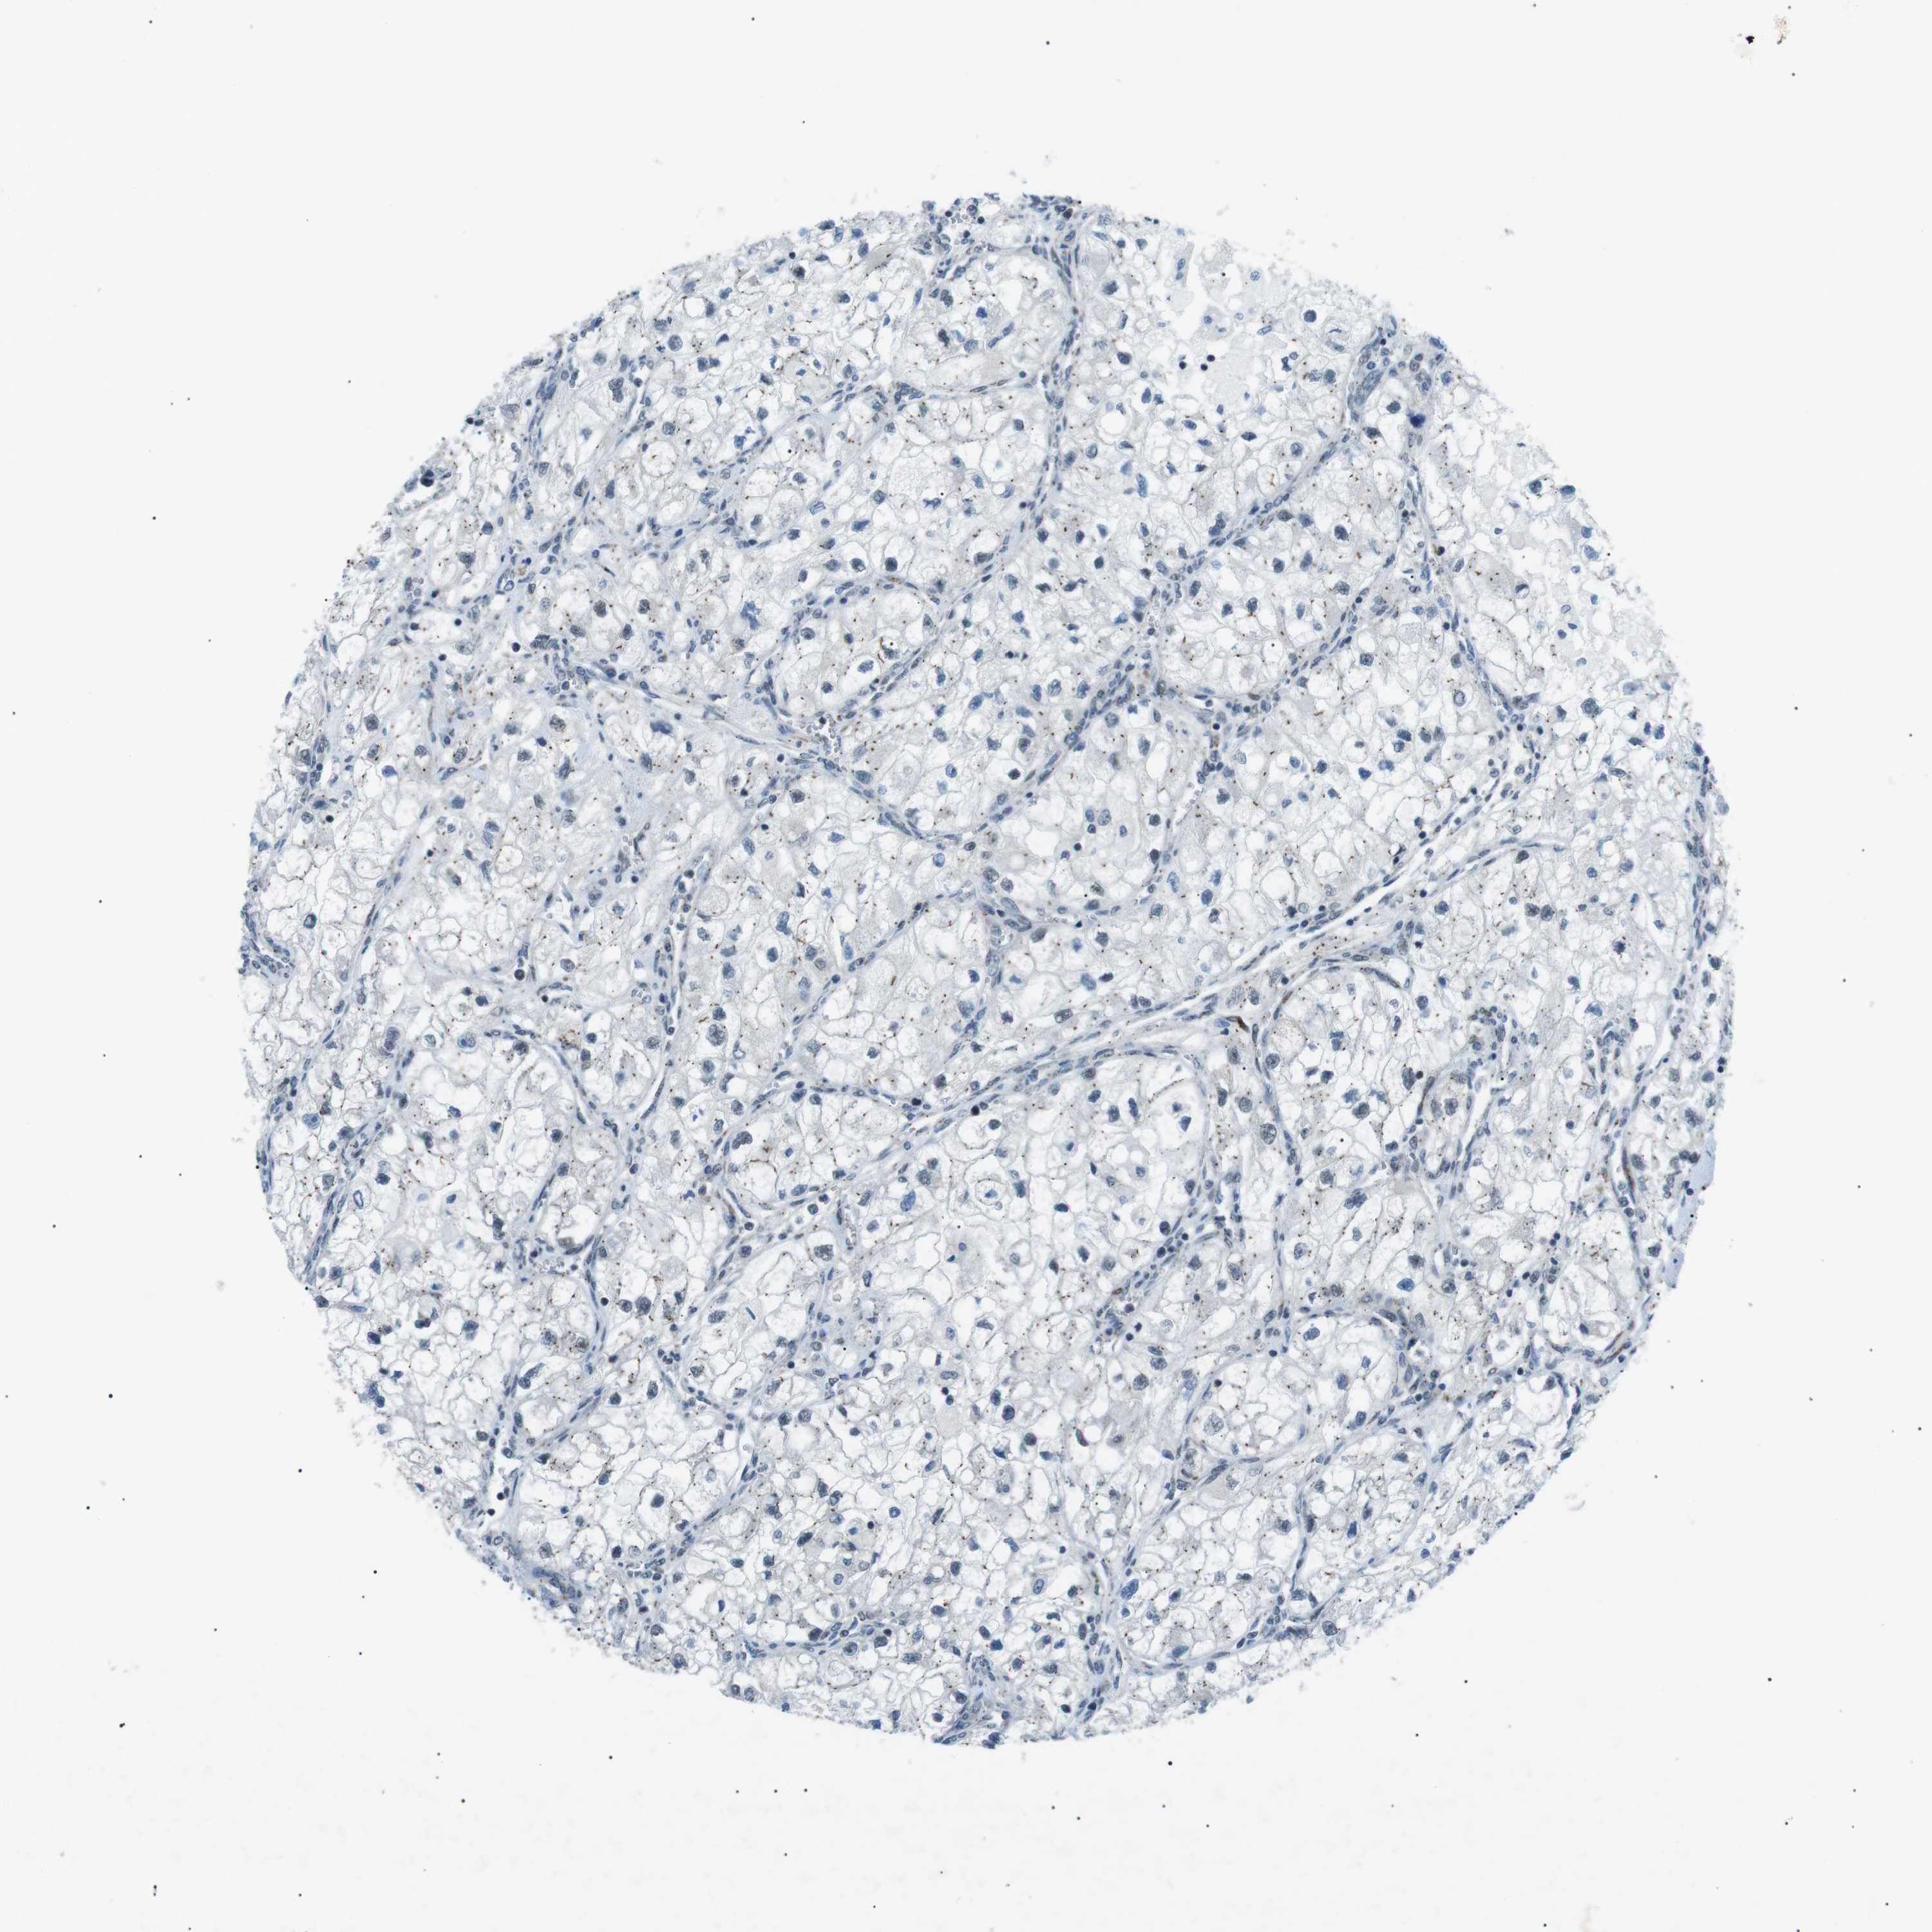

KIDNEY RENAL CLEAR CELL CARCINOMA (TCGA) - Interactive survival scatter ploti

The Survival Scatter plot shows the clinical status (i.e. dead or alive) for all individuals in the patient cohort, based on the same data that underlies the corresponding Kaplan-Meier plots. Patients that are alive at last time for follow-up are shown in blue and patients who have died during the study are shown in red.

The x-axis shows the expression levels (FPKM) of the investigated gene in the tumor tissue at the time of diagnosis. The y-axis shows the follow-up time after diagnosis (years). Both axes are complimented with kernel density curves demonstrating the data density over the axes. The top density plot shows the expression levels (FPKM) distribution among dead (red) and alive patients (blue). The right density plot shows the data density of the survived years of dead patients with high and low expression levels respectively, stratified using the cutoff indicated by the vertical dashed line through the Survival Scatter plot. This cutoff is automatically defined based on the FPKM cutoff that minimizes the p-score. The cutoff can be changed by dragging the vertical line or by entering a cutoff value in the square labeled "Current cut-off".

Under the Survival Scatter plot the p-score landscape (black curve; left axis) is shown together with dead median separation (red curve; right axis). Dead median separation is the difference in median mRNA expression between patients who have died with high and low expression, respectively. It is calculated as follows: median FPKM expression of dead patients with high expression - median FPKM expression of dead patients with low expression. This is intended to aid the user in visually exploring custom cutoffs and the associated p-scores and dead median separation.

Individual patient data is displayed and can be filtered by clicking on one or more of the category buttons on the top of the page. Categories describing expression level and patient information include: high, low, alive, dead, female, male and tumor stages. The scale of the x-axis can be toggled between linear and log-scale by clicking on the "x log" button. Mouse-over function shows TCGA ID, patient information and mRNA expression (FPKM) for each patient.

& Survival analysisi

Kaplan-Meier plots summarize results from analysis of correlation between mRNA expression level and patient survival. Patients were divided based on level of expression into one of the two groups "low" (under cut off) or "high" (over cut off). X-axis shows time for survival (years) and y-axis shows the probability of survival, where 1.0 corresponds to 100 percent.

ARID5B is validated prognostic, high expression is favorable in Kidney Renal Clear Cell Carcinoma (TCGA)

Best expression cut offi

: 12.86

Average pTPM 22.4

Number of samples 521